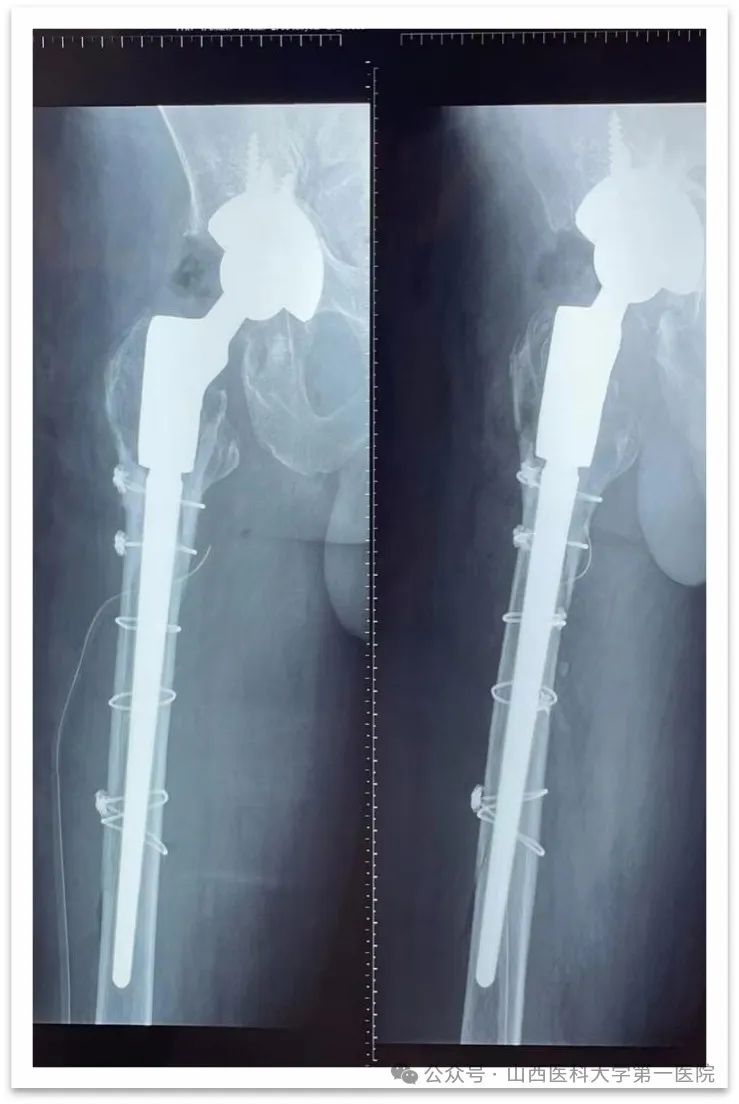

髋关节翻修手术

同时还在多项技术上实现了零的突破,杨自权主任团队在山西省内开展了首例反式肩关节置换术治疗巨大肩袖损伤,完成了肩关节Latarjet手术(喙突截骨移位术)治疗复发性肩关节脱位以及膝关节单髁关节置换术和复杂髋、膝关节翻修手术等,各类四级手术数量有了较高增长,人工关节置换数量与去年同期相比有了超300%的增幅。